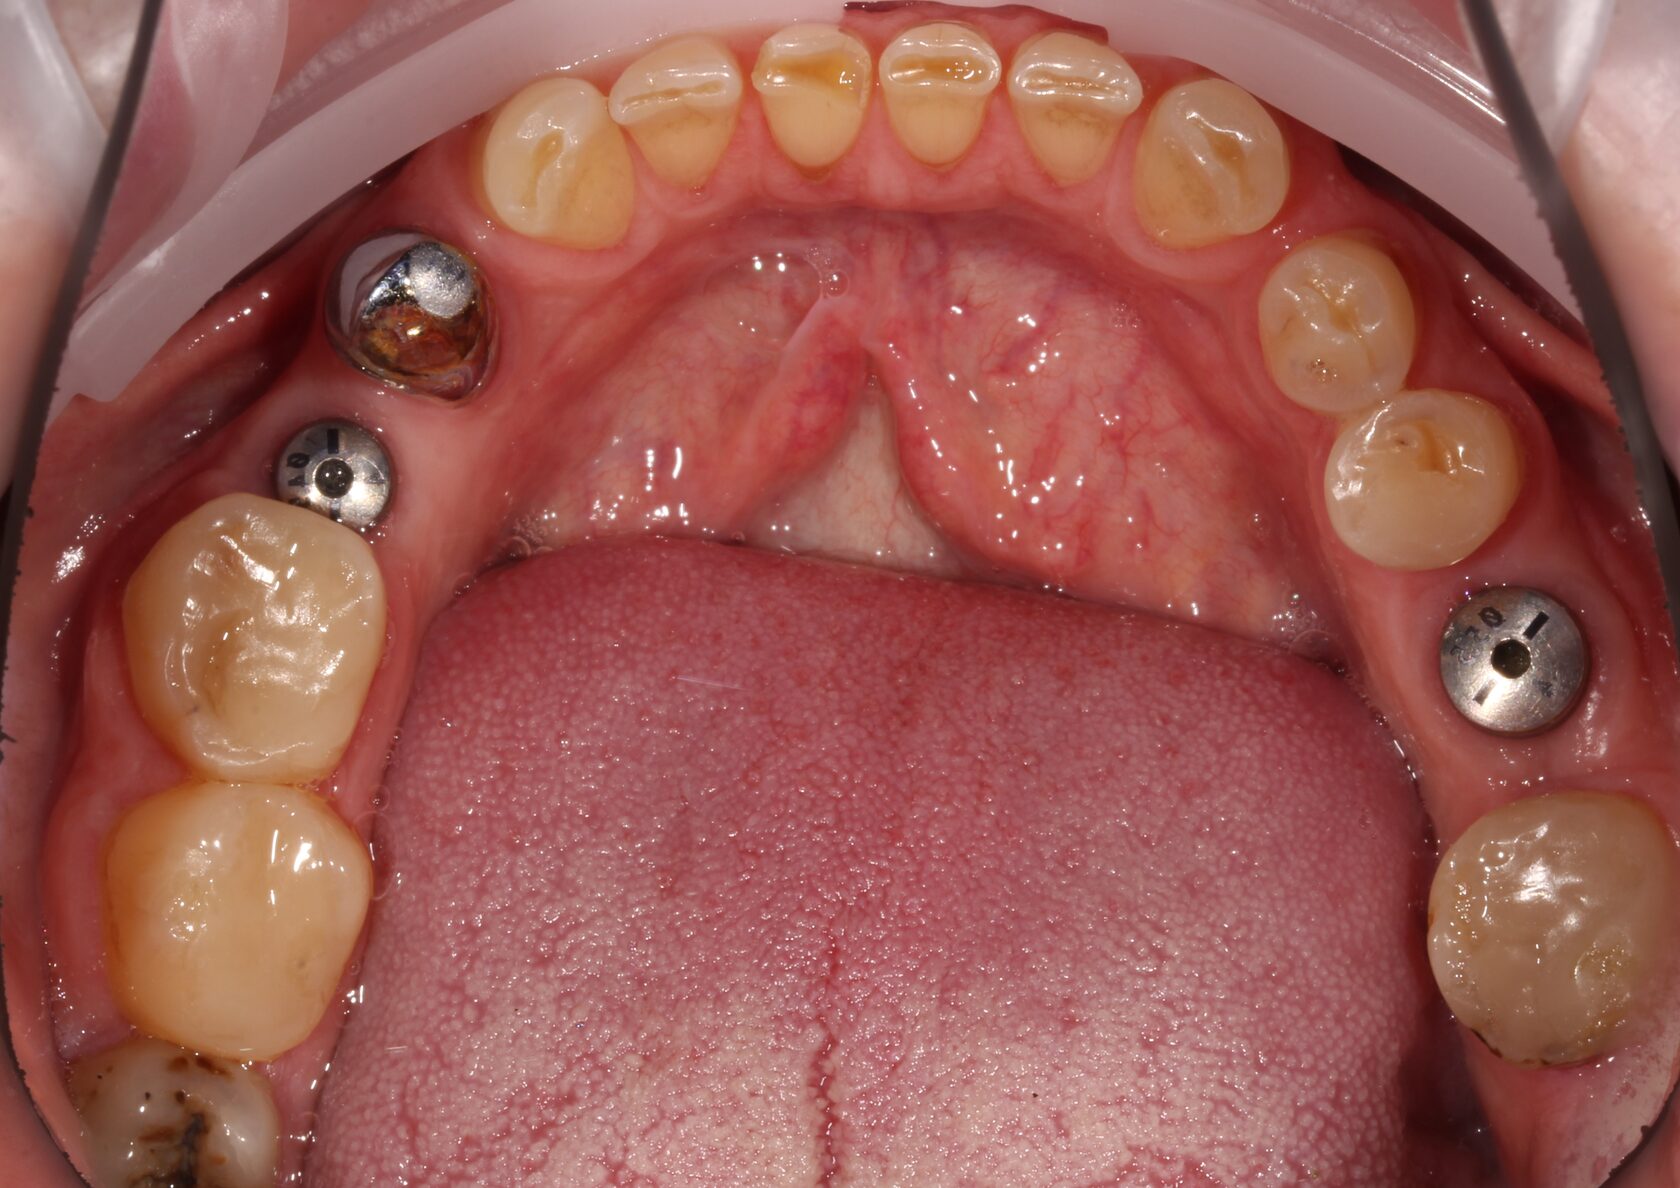

В данном клиническом случае представлена комплексная работа, состоящая из:

1 Терапевтический этап - лечение кариеса, подготовка корневых каналов и восстановление

культей зубов для установки коронок.

2 Хирургчий этап - удаление 2-х зубов с одномоментной дентальной имплантацией.

3 Сложное функционально-эстетическое протезирование (завышение прикуса на временных

коронках, стабилизация мышечного тонуса и позиции ВНЧС, перевод временных конструкций

в постоянные).

Длительность лечения составила более 1 год.